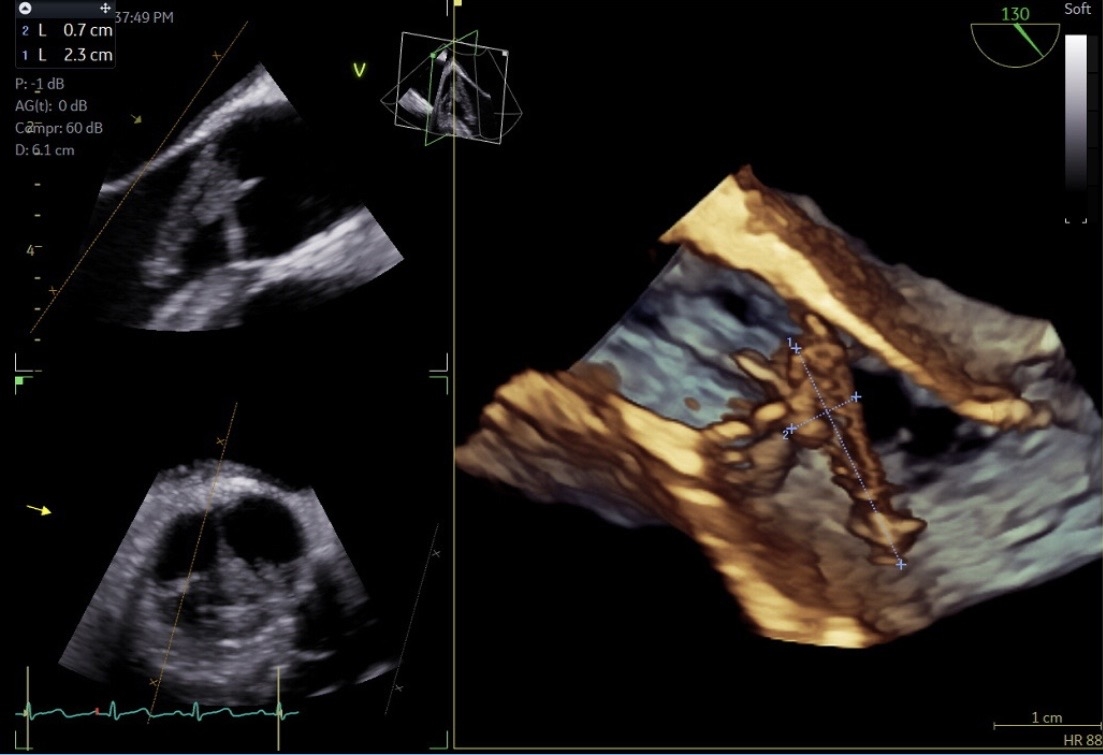

A 36-year-old woman, with drug use disorder was found unconscious with fentanyl and needles nearby. On initial evaluation, she met criteria for systemic inflammatory response syndrome: fever (T 101°F), tachycardia (HR 142 bpm), and hypotension (BP 70/43 mmHg). She was unresponsive to noxious stimuli and had a 15 cm chronic soft tissue ulcer on her right leg. Immediate management was started including endotracheal intubation, mechanical ventilation, followed by intravenous fluid resuscitation, vasopressors, and empiric Meropenem due to documented beta-lactam anaphylaxis. Laboratory studies were remarkable for elevated white blood cell count (36,700/μL), procalcitonin (17 ng/mL), CRP (13 mg/dL), ESR (110 mm/h), and lactate (7 mmol/L). Acute ischemic infarcts in bilateral frontoparietal regions and a punctate infarct in the right cerebellum were demonstrated on computerized tomography. Transthoracic and transesophageal echocardiography identified a 23 mm mobile vegetation on the aortic valve with severe regurgitation. Serratia marcescens, a gram negative fermenter bacilli susceptible to Meropenem, grew on blood and wound cultures. On hospital day 3, severe neurological deficit was observed due to hemorrhagic transformación of the left middle cerebral artery territory infarct.